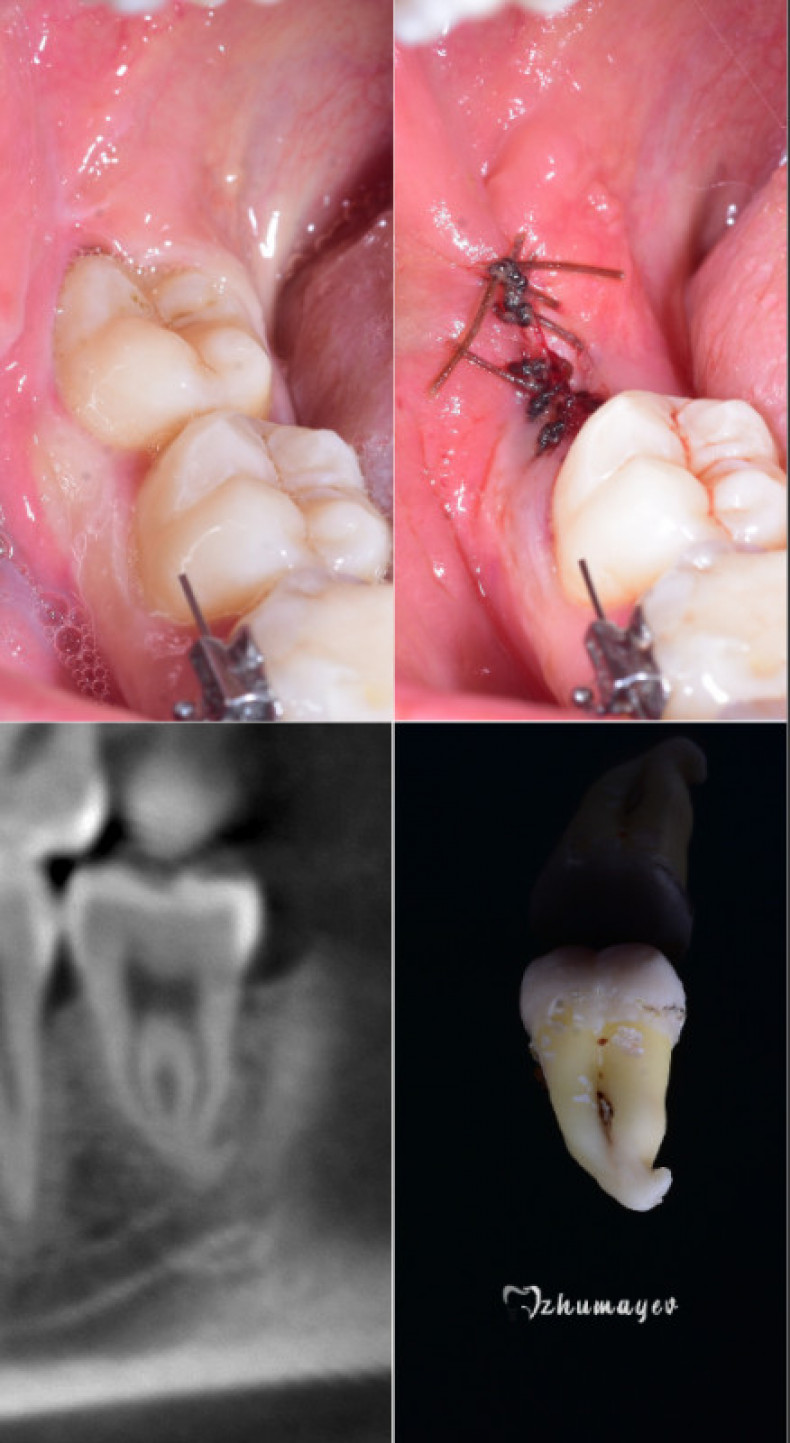

| ✅ Стоматолог Вепа Джумаев | 1300 грн |